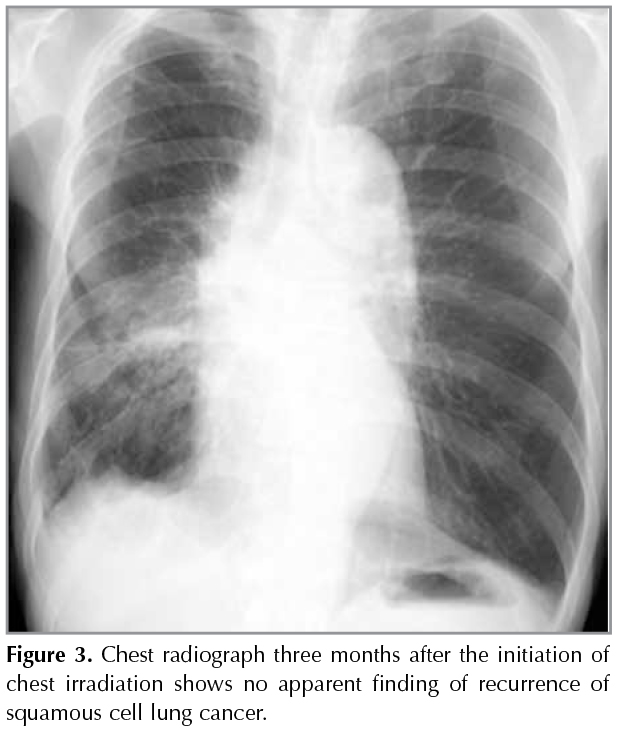

A mass was detected in a 64-year-old man with haemodialysis independent renal impairment undergoing a routine chest X-Ray (Figure 1). Thirteen years ago, the patient had renal biopsy for the correct diagnosis of nephrotic syndrome, and diagnosed as having IgA nephropathy. He treated the disease with prednisolone for ten years. The patient had cough and dyspnea on effort for three months. He smoked one pack-year for 25 years. Chest computed tomography revealed a mass in the right lung with ipsilateral mediastinal lymphadenopathy. There was small amount of pleural fluid in the right hemithorax, which was evaluated as a malignant pleural fluid clinically (Figure 1). Laboratory testing revealed blood ureanitrogen (BUN) 46.0 mg/dL and creatinine (Cre) 2.86 mg/dL. Histopathological analysis obtained by transbronchial biopsy showed squamous cell cancer (Figure 2). A brain computed tomography, abdominal echogram and bone scintigram revealed nodistant metastasis. Due to his impaired renal function, the patient received thoracic irradiation (2 Gy/day, total 50 Gy). He had no additional chemotherapy. On chest radiograph and CT scan three months after the initiation of chest irradiation, volume loss of the right lung due to post-irradiation change was observed, but no apparent finding of recurrence of squamous cell lung cancer was found (Figure 3). During the follow-up period, the patient developed pneumonia twice and herpes zoster in his left back. At these times, his renal function was tentatively deteriorated with BUN 83.0 mg/dL and Cre 5.35 mg/dlL. Fortunately, however, his renal function unexpectedly returned to the revel with BUN 25.0 mg/dL and Cre 2.07 mg/dL 15 months after the thoracic irradiation for the tumor. The patient is now followed up in our outpatient office.